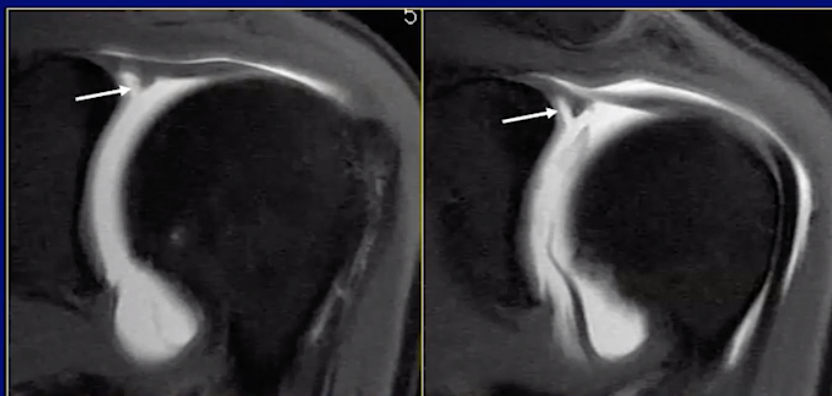

Bucket Handle SLAP Tear of Labrum

Snyder Classification of Labral Tears

• SLAP 2

• Basically SLAP 1 that is deeper and more focal

• Depth > 50%

• SLAP 3

• Essentially bucket handle tear for the labrum

• Basically tear in labrum where there is labrum on both sides like a cookie

• SLAP 4

• Biceps involved

SLAP 2